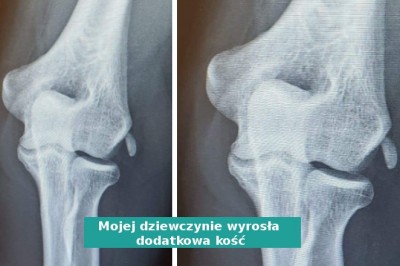

Istnieją odkrycia, które wprawiają nas w osłupienie, nawet jeśli wydaje nam się, że widzieliśmy już wszystko. Takie wyjątkowe rzeczy mogą kryć się tuż pod naszym nosem - chociażby kobieta, której ciało wyhodowało dodatkową kość. Na szczęście, dzięki Inter...